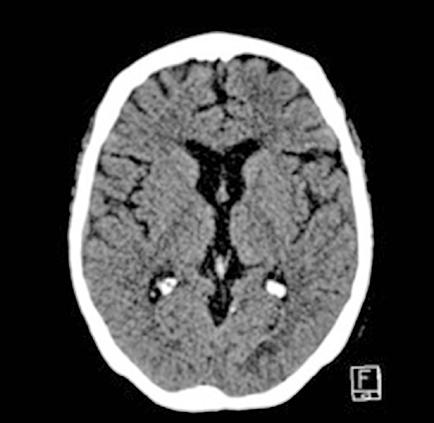

Se realiza medulograma, con el diagnóstico de síndrome mielodisplásico con displasia unilínea (megacariocítica) e hipoplasia eritroide. Asimismo, destaca vacuolización en precursores mieloides y eritroide (Figura 2), motivo por el que se solicita estudio molecular en médula ósea dirigido a estudio de mutaciones en el gen UBA1.

En el estudio citogenético en médula ósea mostró un cariotipo normal. Mientras, el estudio molecular mostró la presencia de alteración para el gen UBA1 detectándose la mutación c.122T>C (p.Met41Thr) en el gen UBA1. El gen JAK2V617F no está mutado.

Dados estos hallazgos se diagnostica al paciente de síndrome de VEXAS asociado a síndrome mielodisplásico unilínea (megacariocítica) de riesgo IPPS bajo e IPSS-R bajo. Tras el diagnostico se inicia tratamiento con tocilizumab intravenoso mensual y eritropoyetina semanal.

Las vacuolas son el hallazgo morfológico característico de esta patología, pudiendo observarse en médula ósea en los precursores mieloides y eritroides. Sin embargo, la presencia de vacuolas es un dato inespecífico que puede observarse en distintas situaciones: intoxicación por alcohol, déficit de zinc o cobre, neoplasias mieloides. Tampoco, se considera una alteración morfológica sugestiva de displasia. Según un reciente estudio retrospectivo publicado por Lacombe et al, la presencia de 10% o más precursores mieloides con más de una vacuola se asocia a síndrome de VEXAS con alta sensibilidad y especificidad (2,3).

Respecto al estudio genético, es necesario confirmar la mutación en UBA1. El gen UBA1 es un gen ligado al X. Por lo tanto, se encuentra en varones, se han descrito casos aislados en mujeres (2,4). Al tratarse de una mutación somática aparece frecuentemente en edades avanzadas. UBA1 codifica la principal enzima activadora de E1 requerida para el inicio de la señal de ubiquitinación celular. Este mecanismo actúa en la degradación de proteínas. Se han descrito tres mutaciones principalmente: c.122T>C (p.Met41Thr)

(la más frecuente), c.121A>G (p.Met41Val) y c.121A>C (p.Met41Leu). La mayoría de pacientes presentan cariotipo normal 46XY (5).